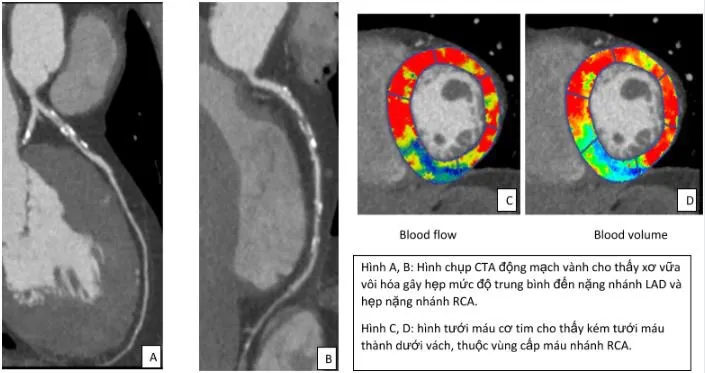

Chụp cắt lớp vi tính tưới máu cơ tim

Chụp CT động mạch vành kết hợp đánh giá tưới máu cơ tim là kỹ thuật chẩn đoán không xâm lấn, cung cấp thông tin chi tiết về cấu trúc và chức năng của động mạch vành. Phương pháp này giúp bác sĩ đánh giá mức độ hẹp/tắc nghẽn và ảnh hưởng của chúng đến lưu lượng máu cơ tim, từ đó đưa ra quyết định điều trị tối ưu. Kỹ thuật này đặc biệt hữu ích trong chẩn đoán đau thắt ngực ổn định và đánh giá bệnh mạch vành.